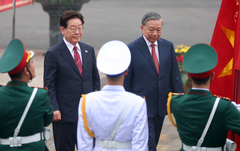

![[서울=뉴시스] 방글라데시에서 5세 남아가 자석 팔찌를 삼켜 긴급 수술을 받았다. (사진=큐레우스 제공)](https://img1.newsis.com/2026/04/23/NISI20260423_0002118800_web.jpg?rnd=20260423144112)

[서울=뉴시스] 방글라데시에서 5세 남아가 자석 팔찌를 삼켜 긴급 수술을 받았다. (사진=큐레우스 제공)

[서울=뉴시스]이기주 인턴 기자 = 성인용 자석 팔찌의 구슬을 삼킨 어린이가 장기에 구멍이 뚫리는 치명적인 손상을 입고 긴급 수술을 받은 사례가 알려져 보호자들의 주의가 요구된다.

23일 국제 학술지 큐레우스(Cureus)에 따르면 방글라데시 다카의 아스가르 알리 병원 의료진은 자석 구슬을 삼킨 5세 남아의 치료 사례를 공개했다.

의료진에 따르면 아이는 3일간 복통과 메스꺼움을 호소하다 병원을 찾았으며, 검사 당시 배꼽 주변의 심한 통증과 함께 빈맥 증상을 보였다. 복부 엑스레이에서는 구슬 형태의 이물질이 일렬로 연결된 모습으로 확인됐다.

이후 아이의 장난감 상자에서 유사한 구슬이 발견되면서, 해당 이물질이 장난감이 아닌 성인용 자석 팔찌 일부인 것으로 드러났다. 의료진은 내시경으로 위 안에 있던 구슬 5개를 제거했지만, 나머지 4개는 이미 위벽을 뚫고 깊이 박혀 있어 추가 제거가 어려운 상태였다. 이에 따라 환아 상태 악화를 우려해 긴급 개복 수술이 진행됐다.

수술 과정에서는 자석 사고 중에서도 드문 합병증인 위 결장 누공이 확인됐다. 서로 다른 장기에 위치한 자석들이 강한 자성으로 서로를 끌어당기면서 장기 벽을 압박했고 이 과정에서 조직 괴사가 발생해 위와 대장 사이에 비정상적인 통로가 형성된 것이다.

의료진은 자석들이 위와 대장 벽에 단단히 박혀 있었고 주변 조직에는 심각한 염증과 경화가 진행된 상태였다고 설명했다. 특히 여러 개의 자석이 서로 다른 위치에서 작용하면서 장기를 관통해 붙는 현상이 치명적인 결과로 이어졌다고 강조했다.

결국 의료진은 유착 부위를 분리하고 모든 자석을 제거한 뒤 손상된 위와 대장을 봉합했다. 회수된 구슬은 지름 4mm 크기의 강력한 네오디뮴 자석으로 확인됐다. 아이는 수술 후 6일 만에 합병증 없이 회복해 퇴원했다.

전문가들은 자석 관련 사고의 위험성을 거듭 경고하고 있다. 미국소아과학회는 "여러 개의 자석을 삼킬 경우 증상이 없더라도 장기 손상이 빠르게 진행될 수 있다"며 "자석 장난감뿐 아니라 성인용 자석 제품도 어린이 손이 닿지 않는 곳에 보관해야 한다"고 당부했다.